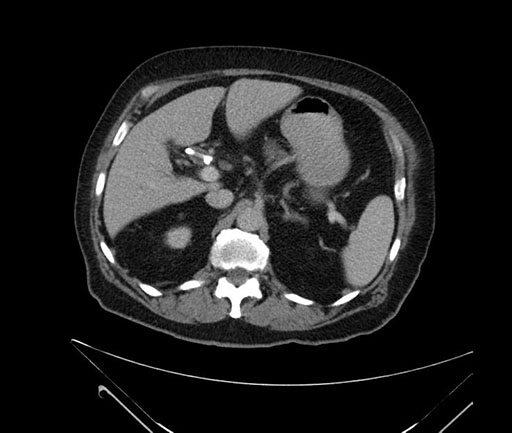

Axial - 3 months prior

Axial - stented

Coronal - stented

Imaging analysis

Based on your CT findings, which issue(s) would give reason for "planned slowing down moment(s)" in this case?

Considering a standard Whipple procedure, what step(s) of the operation would you do differently in this case?